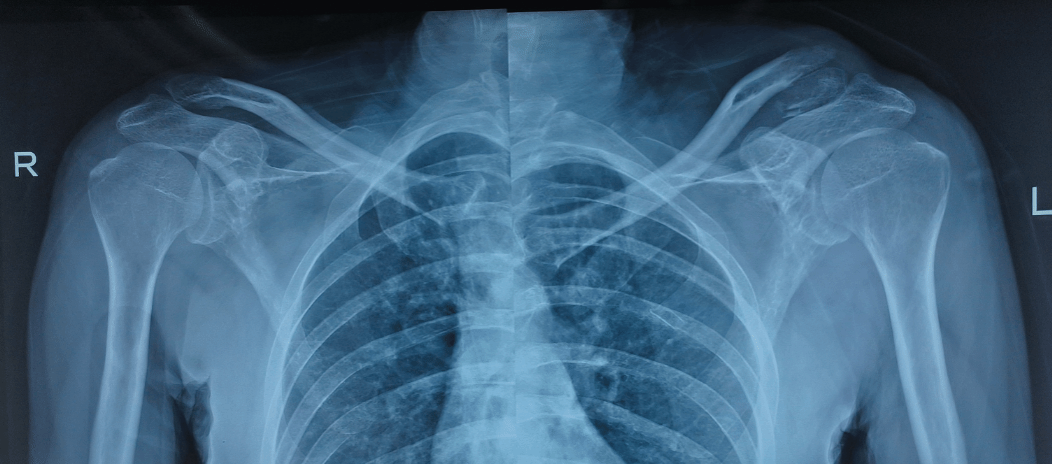

近日,我院骨科中心关节与足踝病区张晨教授团队收治了一名特殊的骨折患者。该患者因车祸致伤由急诊入院,外院X线检查提示左侧锁骨远端骨折合并肩锁关节脱位。

入院后,骨科中心关节与足踝病区张晨教授团队迅速展开术前评估,完善肩关节三维重建及MRI等检查。结果显示,患者左侧锁骨远端严重毁损,合并肩锁关节脱位。传统钢板复位难度较大,且术后功能恢复存在挑战,患者对二次手术取出钢板存在较大焦虑和抵触情绪。团队在积极完善术前准备的同时,重新评估并优化手术方案。经过慎重考量,团队决定采用创新的悬吊缝合桥技术,以期达到良好的治疗效果,同时避免患者因钢板取出而经历二次手术。经充分的术前讨论并取得患者及家属知情同意后,手术于2025年3月6日顺利实施。术中,骨折端对位良好,肩锁关节复位稳定,患者现已出院并在康复指导下开展功能训练。

术前肩关节三维CT